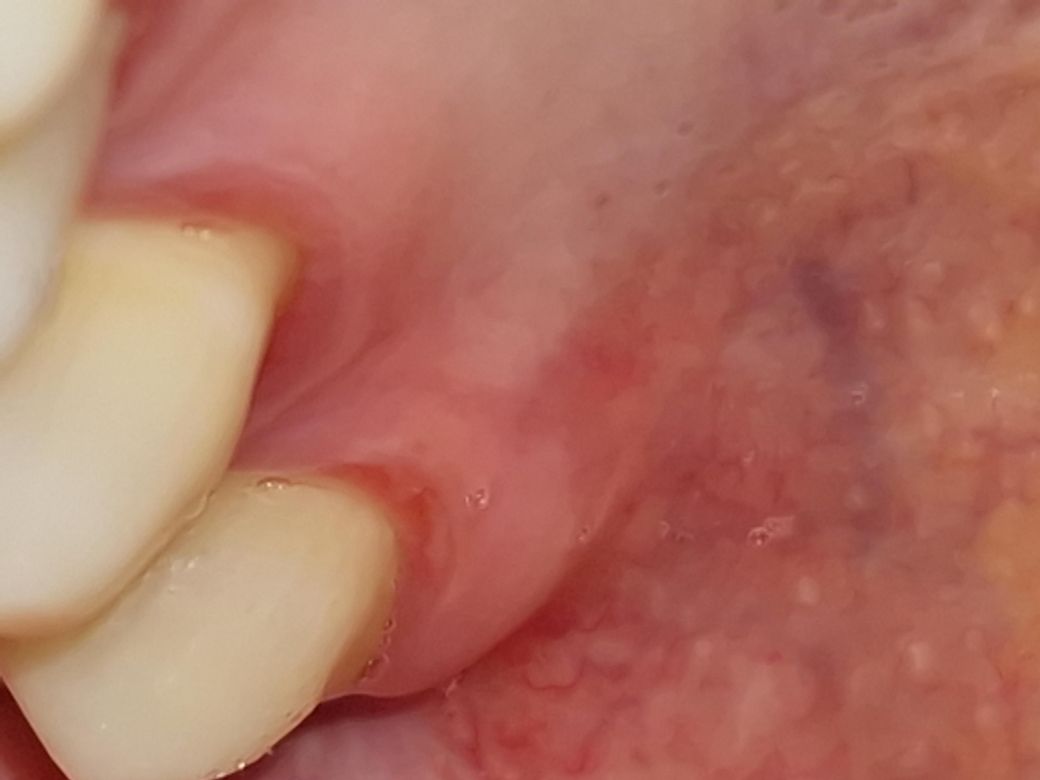

잇몸 상처난 것 같아요. 사진 첨부했어요.

위쪽 어금니 안쪽 잇몸이 까진 것 처럼 혀로 만졌을때 덜렁거리고 따끔한 통증이 있어요.

어제까진 안 그랬는데 그냥 가만히 놔두면 자연치유 되는지 궁금합니다

잇몸이 자극을 받아서 생긴 상처 같습니다 .최대한 상처가 가지 않도록 해주시면 시간이 지나면 괜찮아 지실꺼에요.

위쪽 어금니 안쪽 잇몸이 까진 것 처럼 혀로 만졌을때 덜렁거리고 따끔한 통증이 있는 건 구내염일 가능성이 높습니다.안녕하세요. 송우식 치과의사입니다.

잇몸 단순 상처로 보입니다. 그냥두면 저절로 아물 것으로 보입니다. 식사할 때 따가울 수 있으니 매운거나 뜨거운 것은 조심해야 합니다.

잇몸에 미약한 염증이 있거나 자극적인 음식을 먹어 잇몸이 헐은 것 같습니다 일반적으로 며칠이면 자연스럽게 호전될 것 같습니다